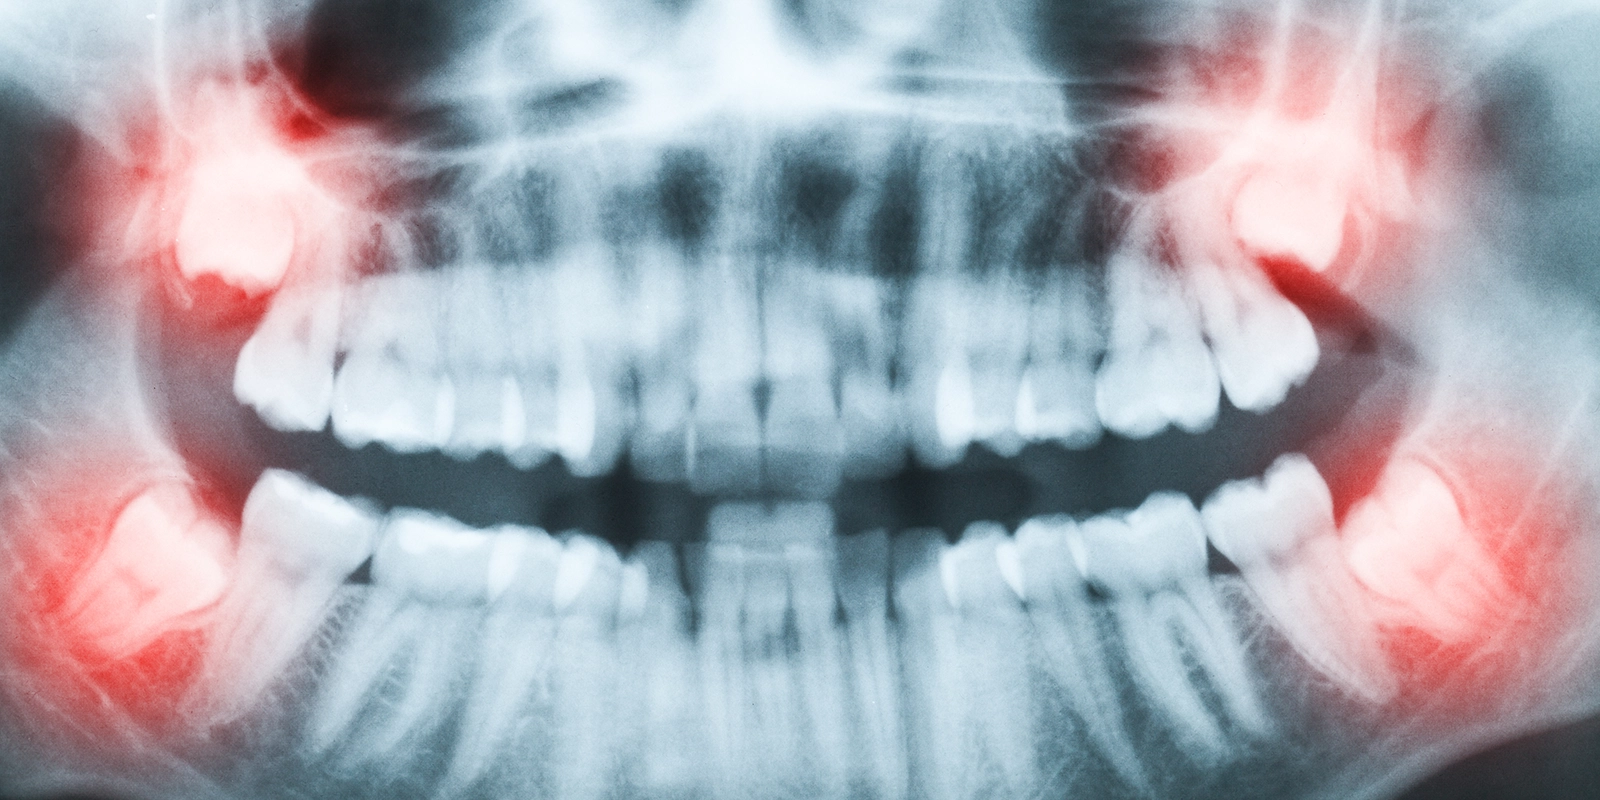

現代人の顎は小さくなる傾向にあり、親知らずが生えるためのスペースが不足していることが多いです。そのため、まっすぐ正常に生えることは稀で、斜めに生えたり、一部だけ顔を出したり、完全に埋まったままになることが一般的です。このような状況により、親知らず周辺は清掃性が悪くなりがちで、虫歯や歯周病にかかりやすく、治療も成功しにくいという特徴があります。

親知らずの生え方による分類

垂直埋伏

親知らずは正常な方向を向いているが、スペース不足のため完全に萌出できない状態です。比較的抜歯しやすいケースが多いです。

水平埋伏

親知らずが横向きに倒れている状態です。隣の歯の根を圧迫したり、清掃が困難になりやすいため、抜歯が推奨されることが多いです。

斜め埋伏

親知らずが斜めに傾いている状態です。傾きの程度により抜歯の難易度が変わります。

完全埋伏

親知らずが完全に骨の中に埋まっている状態です。症状がなければ経過観察することもありますが、嚢胞形成のリスクがある場合は抜歯を検討します。